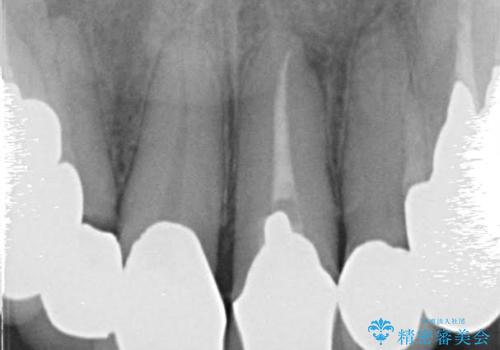

・虫歯がとりきれていない

・接触部分がガタガタで適合の悪い金属

・全く無菌の努力がされていない根管治療

など、いい加減な治療は「治療」ではなく、むしろ医原性に歯の寿命を短くします。

最もよくないのは、クオリティの低い治療を何度も繰り返すことです。